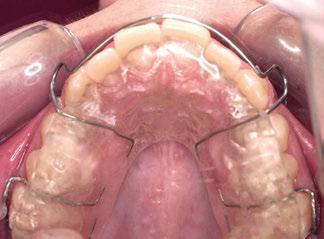

Tras la terminación de la fase ortopédica, se continuó con la colocación de los brackets

mencionados anteriormente. La prescripción de estos fue de alto torque en los incisivos superiores y en los cuatro caninos, y de bajo en los incisivos inferiores. Tras 12 meses desde la colocación de los brackets y una vez conseguida la normalización de las relaciones oclusales, se colocaron unos retenedores fijos de canino a canino en ambas arcadas de acero trenzado de 6 hilos (.017” superior y .019” inferior) y un guarda de contención nocturna hasta la terminación del crecimiento puberal.

Transcurridos 7 meses, se sustituyó por un Twin Block para un segundo y definitivo avance (figuras 12 a 16).

A fin de mejorar el patrón facial y

permitir la erupción de los molares inferiores (estos molares no deben poseer ganchos Adams ya que podrían dificultar su erupción) se fueron desbastando los bloques del acrílico superior progresivamente a razón de 1 mm al mes.

Este último aparato funcional se mantuvo en boca durante 8 meses, tras haber conseguido la mejoría esperada en cuanto al aspecto facial (figura 17) y las relaciones oclusales (figuras 18 a 22). La mordida abierta lateral producida es fácilmente solucionable en la siguiente fase de tratamiento.

Con el cementado de los brackets de la técnica Universal Smile System

(USS), como se aprecia en las figuras 23 a 25, comienza la segunda fase de tratamiento. Esta duró tan solo 12 meses debido a que gran parte de las relaciones oclusales habían mejorado durante la etapa anterior. Los resultados finales del tratamiento se observan en las figuras 26 a 30 , con la corrección de la clase molar y canina, el resalte y la sobremordida, el centrado de las líneas 1/2 y la curva de Spee. La mejoría en la macro, mini y microestética facial se aprecia en las figuras 31 a 33 , a pesar de la evidente desviación del mentón hacia

Ya que el tratamiento se finalizó antes de la terminación del crecimiento puberal, se colocó a modo de retención un guarda para mantener las arcadas coordinadas hasta el cese de este.

Los retenedores fijos (13, 14) FLAS y FLAI (férula lingual anterosuperior e anteroinferior, respectivamente) de alambre de acero trenzado de 6 hilos, cementados de canino a canino, aportan estabilidad a los sectores anteriores, y el splint o guarda como aparato de contención nocturna hasta la terminación del crecimiento puberal, aporta estabilidad a los resultados conseguidos.